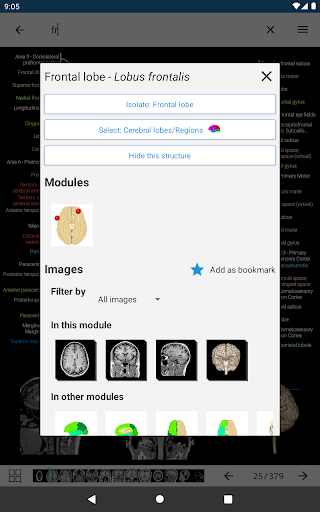

- Toque las etiquetas para mostrar las estructuras anatómicas

- Localice fácilmente las estructuras anatómicas gracias a la búsqueda de índice

- "Filtrar por", en la vista de detalles ahora puede filtrar las imágenes que contienen la estructura anatómica por modalidad

- "Filtrar por", en la vista de detalles ahora puede filtrar las imágenes que contienen la estructura anatómica por modalidad

- Ahora puede ocultar las estructuras una por una (nuevo botón dentro de la ventana emergente de descripción) y visualizarlas nuevamente en el menú derecho